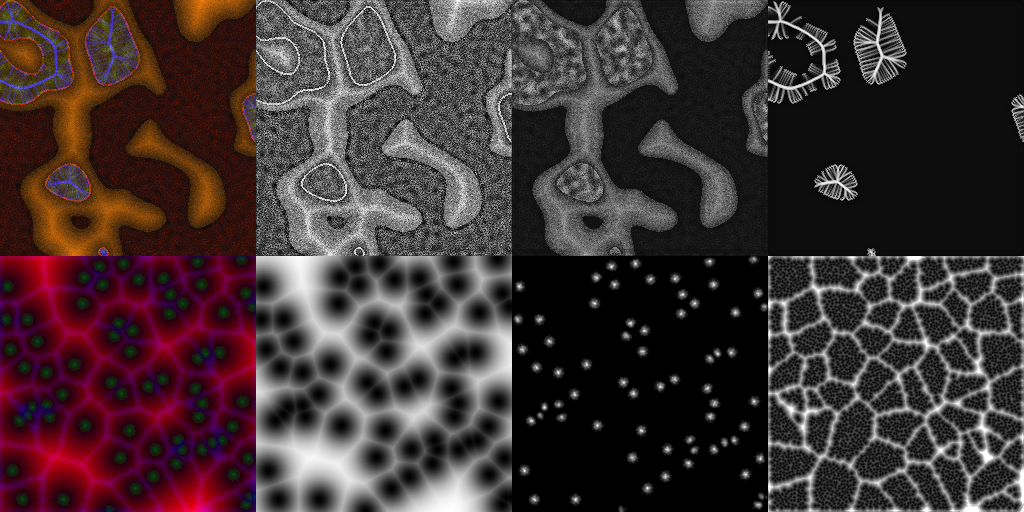

Super-resolution, in-painting, whole-image generation, unpaired style-transfer, and network-constrained image reconstruction each include an aspect of machine-learned image synthesis where the actual ground truth is not known at time of use. It is generally difficult to quantitatively and authoritatively evaluate the quality of synthetic images; however, in mission-critical biomedical scenarios robust evaluation is paramount. In this work, all practical image-to-image comparisons really are relative qualifications, not absolute difference quantifications; and, therefore, meaningful evaluation of generated image quality can be accomplished using the Tversky Index, which is a well-established measure for assessing perceptual similarity. This evaluation procedure is developed and then demonstrated using multiple image data sets, both real and simulated. The main result is that when the subjectivity and intrinsic deficiencies of any feature-encoding choice are put upfront, Tversky's method leads to intuitive results, whereas traditional methods based on summarizing distances in deep feature spaces do not.